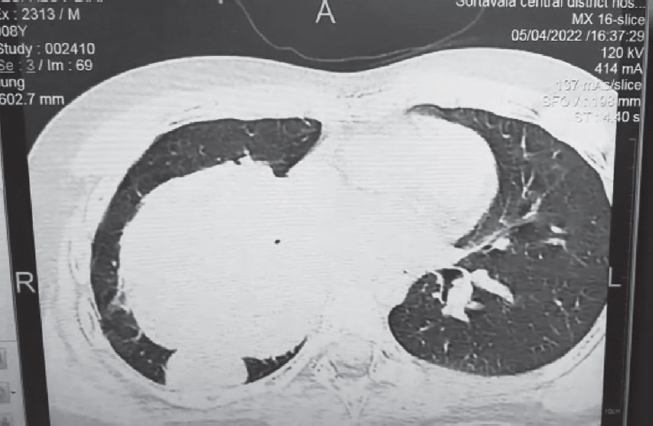

Представлен клинический случай плевропульмональной бластомы у мальчика 8 лет, диагностированной на фоне острой респираторной вирусной инфекции. Ребенок заболел остро с подъемом температуры и малопродуктивным кашлем. Участковым педиатром состояние расценено как течение острой респираторной вирусной инфекции, назначена симптоматическая терапия. Через 8 дней от начала заболевания на фоне полного благополучия отмечается резкое ухудшение состояния в виде одышки, отказа от еды и питья, слабости. Ребенок госпитализируется в центральную районную больницу, проводится дифференциальная диагностика с пневмонией. По данным обследования (обзорная рентгенограмма и спиральная компьютерная томография органов грудной клетки) в правом легком визуализируется объемное образование больших размеров с ровными контурами. Пациент переводится в специализированный стационар Санкт-Петербурга. После проведения магнитно-резонансной томографии органов грудной клетки с контрастированием, взятия биопсионного материала и выполнения гистологического исследования у пациента диагностирована опухоль правого легкого — плевропульмональная бластома тип II.